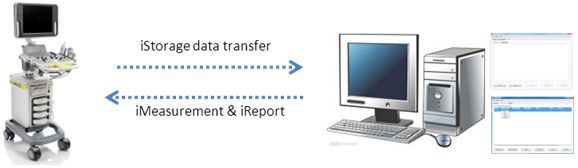

iStorageTM?/ iMeasurementTM?/ iReportTM

iStorage: –љ–µ–њ–Њ—Б—А–µ–і—Б—В–≤–µ–љ–љ–∞—П –њ–µ—А–µ–і–∞—З–∞ –Є–Ј–Њ–±—А–∞–ґ–µ–љ–Є–є –Є –Њ—В—З–µ—В–Њ–≤ –љ–∞ –Я–Ъ –њ–Њ —Б–µ—В–µ–≤–Њ–Љ—Г –Ї–∞–±–µ–ї—О.

iMeasurement & iReport: –њ—А–Њ–≥—А–∞–Љ–Љ–љ–Њ–µ –Њ–±–µ—Б–њ–µ—З–µ–љ–Є–µ –і–ї—П –Я–Ъ, —А–∞–±–Њ—В–∞—О—Й–µ–µ –≤ –Њ—Д—Д–ї–∞–є–љ-—А–µ–ґ–Є–Љ–µ, –і–ї—П —А–∞–±–Њ—В—Л —Б –Ј–∞–і–∞–љ–љ–Њ–є –њ–Њ–ї—М–Ј–Њ–≤–∞—В–µ–ї–µ–Љ —В–∞–±–ї–Є—Ж–Њ–є –Є–Ј–Љ–µ—А–µ–љ–Є–є, —Д–Њ—А–Љ—Г–ї–∞–Љ–Є —А–∞—Б—З–µ—В–∞ –Є —И–∞–±–ї–Њ–љ–∞–Љ–Є –Њ—В—З–µ—В–∞.